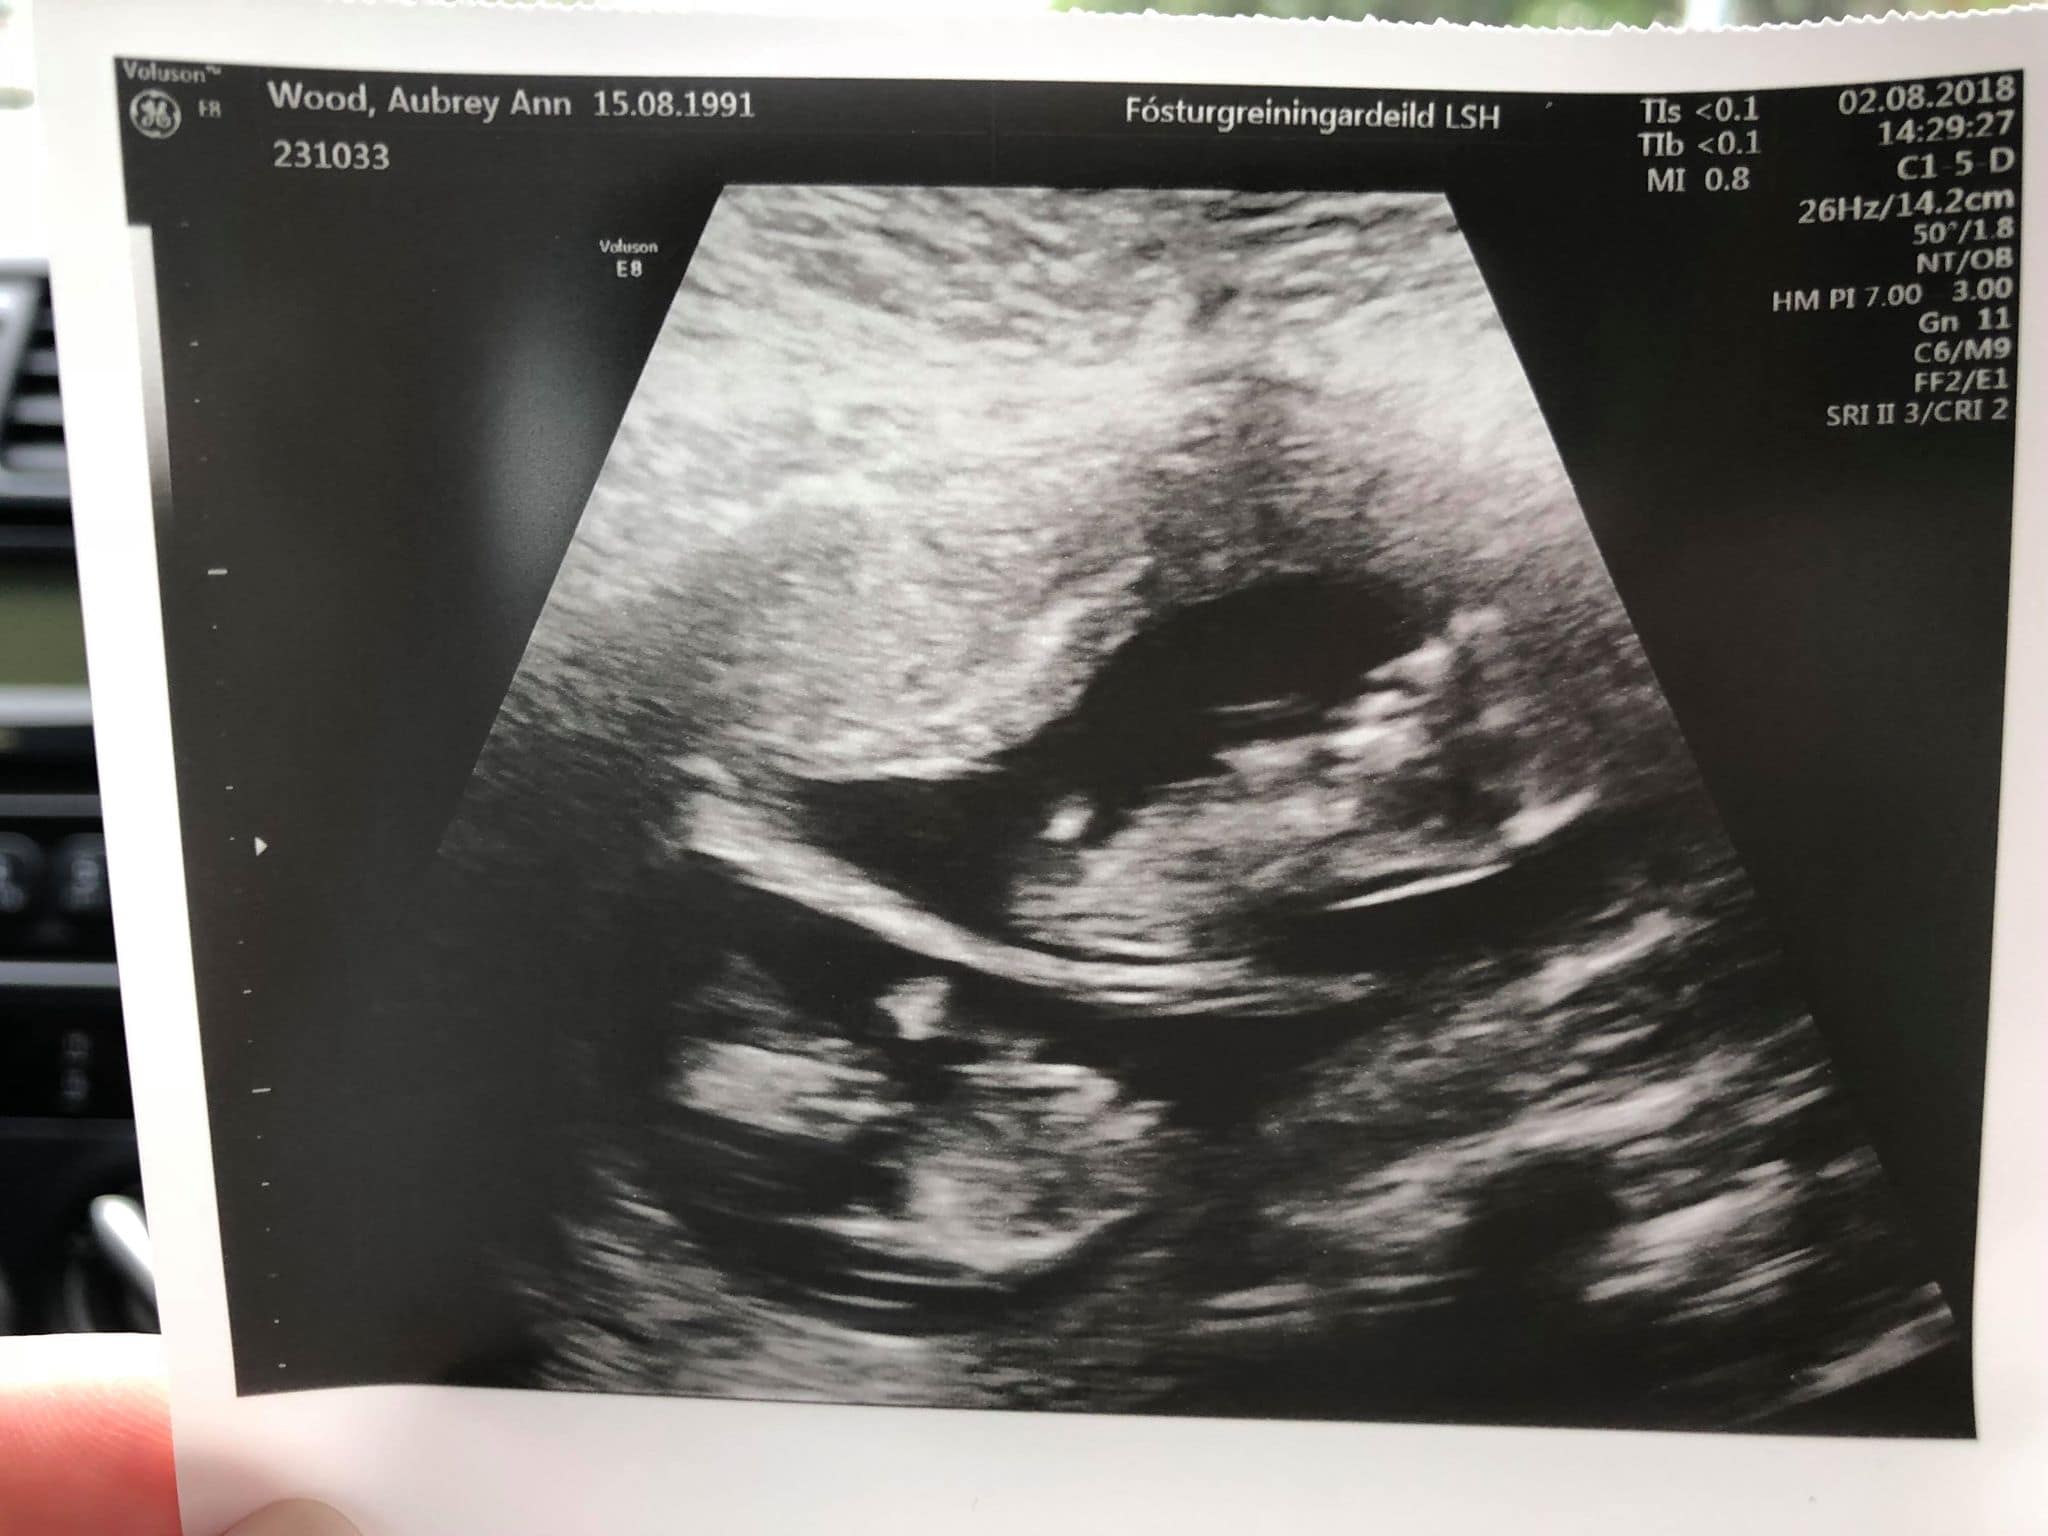

Ultrasound Photos at 12 Weeks Pregnant With Twins